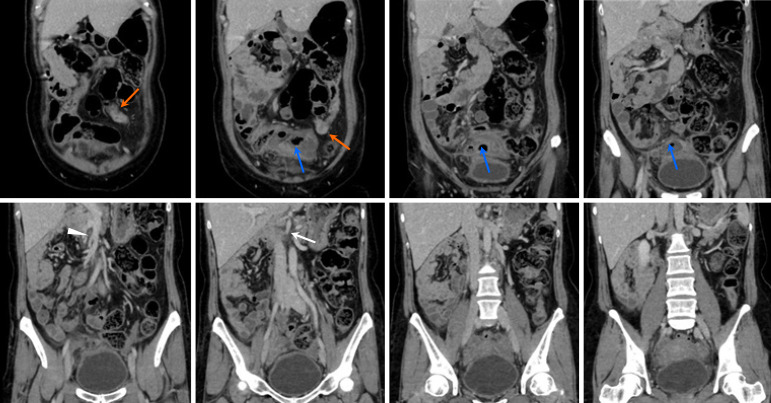

Results: Idiopathic pain was the most common diagnosis (104 cases, 45.2%), followed by appendicitis (46 cases, 20.0%) and diverticulitis (27 cases, 11.7%). Right lower quadrant pain predominantly revealed appendicitis (20.2%), whereas left lower quadrant pain frequently indicated diverticulitis (12.1%). Nonspecific pain cases have diverse etiologies. Rare conditions included situs inversus (one case) and intestinal malrotation (one case). Pregnancy-related diagnoses included acute appendicitis and uterine fibroid degeneration.